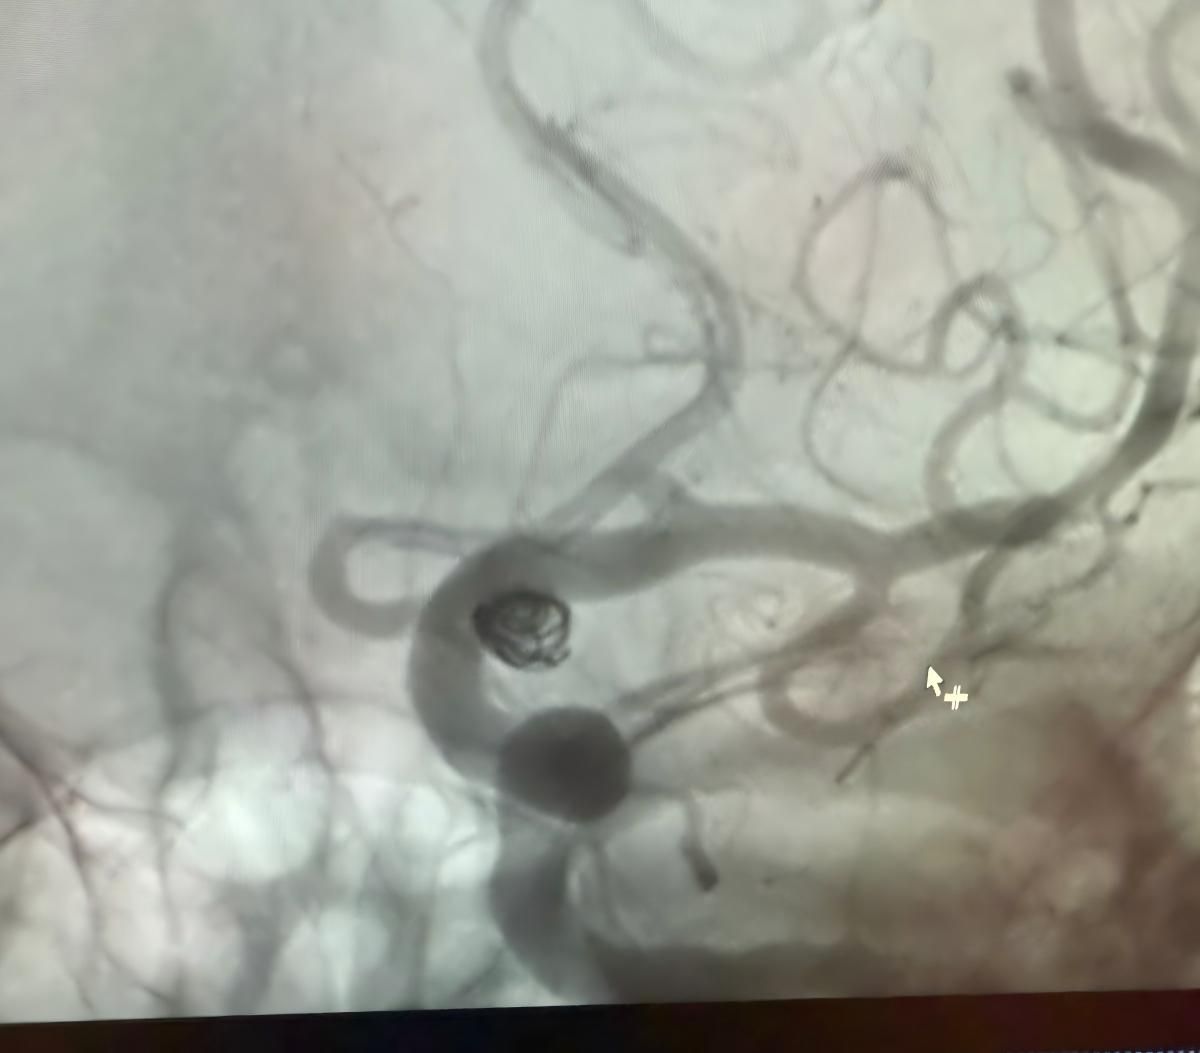

Nos complace compartir un procedimiento exitoso reciente en Clínica Alma Mater, Medellín, realizado por el Dr. Jorge Mutis.

El tratamiento utilizó el Nuva®Desvedor de flujo (TJED-D 5.0-14), Perdenser®Bobina 3D, y el paso de tierra®Microcatéter (TJMC18 Plus) para un aneurisma de arteria comunicante posterior.

Dr. Mutis destacó la excelente visibilidad del dispositivo y señaló que la recuperación fue suave. Expresó su gran satisfacción por el resultado final.